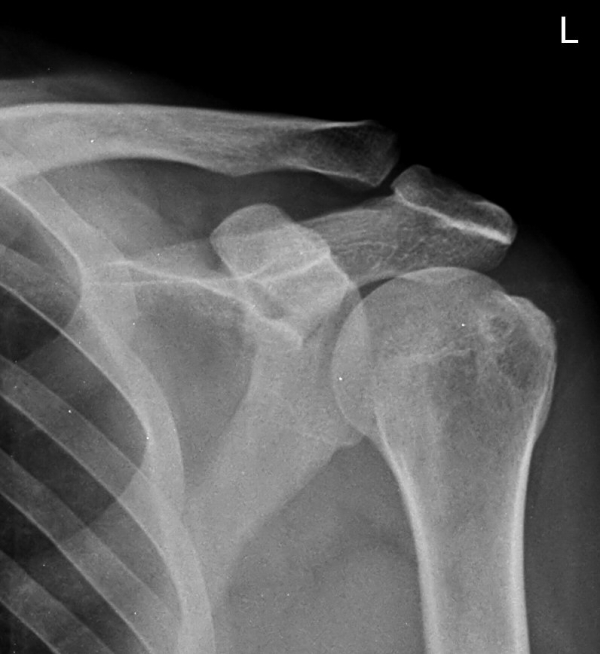

ƯÀÌ °ßºÀ ¾Æ·§¸éÀÇ °æÈ­ ¼Ò°ß ¹× °ßºÀ ¾Æ·¡ ¿¹¸®ÇÑ °ñ±ØÀÌ °üÂûµÊ

¹æ»ç¼±»çÁøÀ̳ª ÀÚ±â°ø¸í°Ë»ç¿¡¼­ °ñ±ØÀÌ °üÂûµÇ°í ±Ø»ó°Ç ÆÄ¿­ÀÌ ÀÖ´Â °æ¿ì °Ë»ç¿¡¼­ º¸ÀÌ´Â

°ñ±ØÀÌ ±Ø»ç°ÇÆÄ¿­ÀÇ ¿øÀÎÀ̶ó°í ÃßÁ¤ÇÒ ¼öµµ ÀÖ´Ù.  ±×·¯³ª ±Ø»ó°ÇÆÄ¿­ÀÌ Ç¥Ãþº¸´Ù´Â ½ÉÃþ¿¡¼­

´õ ¸¹ÀÌ ¹ß»ýÇϰí Áõ»óÀ» ÀÏÀ¸Å°Áö ¾Ê´Â °ñ±ØÀÌ ¸¹Àº Á¡À» °í·ÁÇÒ ¶§ °Ë»ç¿¡¼­ º¸ÀÌ´Â °ñ±ØÀ»

Ä¡·á(°ßºÀ¼ºÇü¼ú)ÀÇ ´ë»óÀ¸·Î ÇÏ´Â °ÍÀº Çϸ®ÀûÀÎ °áÁ¤ÀÌ ¾Æ´Ï´Ù. ÀÌ È¯ÀÚÀÇ °æ¿ìó·³ ±Ø»ó°Ç

³»ÃøÀÇ ºÎÁ¾°ú Ç¥Ãþ ¶Ç´Â ÀüÃþ ÆÄ¿­ÀÌ ÀÖÀ¸¸é¼­ Á¡¾×³¶ÀÇ ºÎÁ¾°ú Ãæµ¹°Ë»ç ½Ã Ãæµ¹ ¼Ò°ßÀ» º¸ÀÌ´Â °æ¿ì¿¡

¹æ»ç¼±À̳ª ÀÚ±â°ø¸í°Ë»ç¿¡¼­ º¸ÀÌ´Â °ñ±ØÀÌ ±Ø»ó°Ç ÆÄ¿­ÀÇ ¿øÀÎÀ¸·Î ÃßÁ¤ÇÒ ¼ö ÀÖ´Ù.